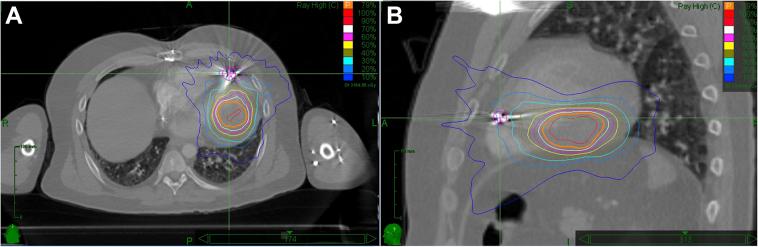

Stereotactic radiosurgery as a treatment for recurrent ventricular tachycardia associated with cardiac fibroma.

HeartRhythm Case Rep. 2018 Oct 24;5(1):44-47. doi: 10.1016/j.hrcr.2018.10.007. eCollection 2019 Jan.